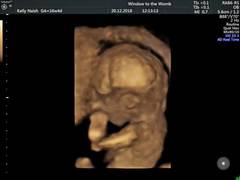

Booked in for a last minute gender scan this morning!!! I'm 18 weeks today and I was just bursting with anticipation!!! Baby was so perfect in the scan!!! They got great images and confirmed the sex!!

kisses4u · 15/12/2018 20:32

we got 4D images which I didn't realise we were getting! She looks just like her big brother 😍

Congratulations @kisses4u! Another little girl in the group 💕How exciting! Lovely pictures too!

So i did mamage to get scan yesterday partly cos i was worried again and felt stomach bit smaller... but all was fab heard heartbeat for the firat time and to my suprise found out that im DEFINITELY having a boy 😂 now the birth is worrying cos hes starting off just like his dad and hes 6'2 and has size 13 feet 😣

Congrats @Swisbest2 &@dreaminofholidays! Aw a little boy! Yup no denying with those pics! Understand how you guys feel - it was Christmas last year that I had my first miscarriage & am feeling like I'm needing lots of reassurance more than usual with kicks and things- doesn't help being so busy that it's harder to notice them 🙁 going to see how today goes but may ring midwife if I don't feel any more movements throughout the day I think...